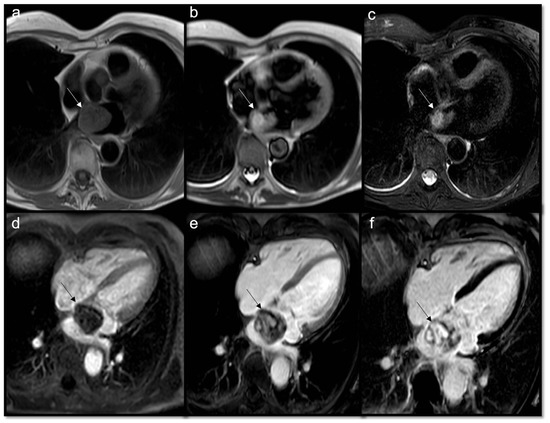

- To assess border, size, and location

- Very useful for stable anatomical relationships of the mass with myocardium (intramyocardial or pedunculated) and with adjacent structures

- To achieve a better anatomic definition than T2w ones

- High signal: lipid content, melanin, blood catabolites (methemoglobin)

- Low signal: indicates fibrosis